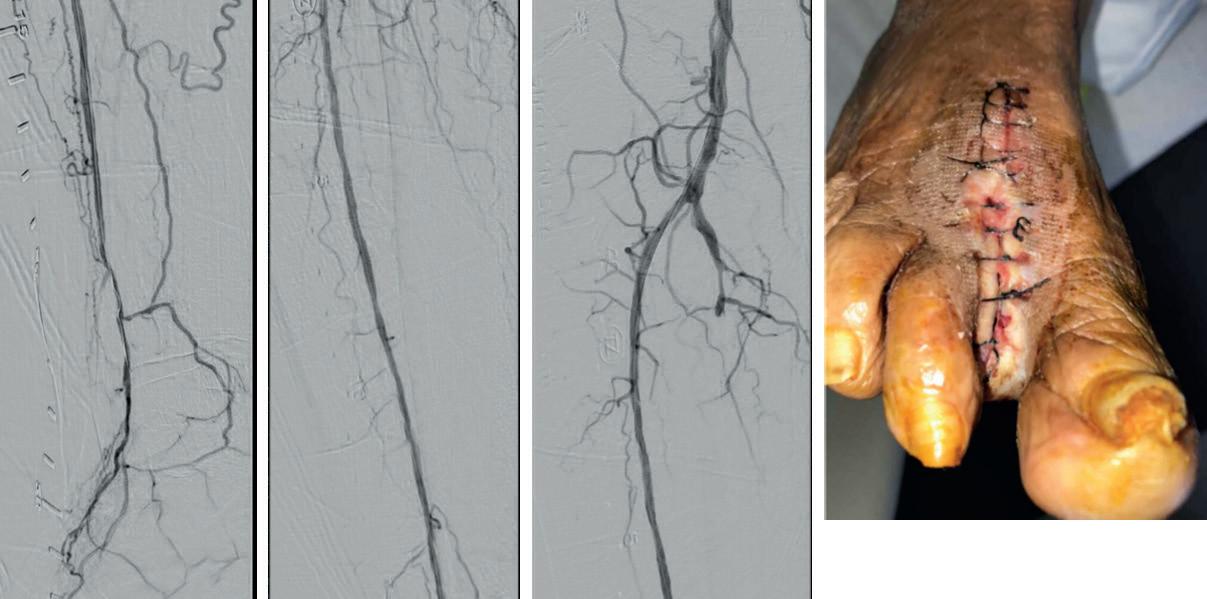

Tackling difficult acute limb ischemia cases with an endovascular-first approach using Lightning Bolt 7 computer assisted vacuum thrombectomy

Adam Reichard, MD, discusses the use of Lightning Bolt 7® computerassisted vacuum thrombectomy (CAVT TM) as a first-line option across a wide spectrum of challenging lower extremity acute limb ischemia (ALI) cases, including patients with Rutherford classification IIb ALI.

Two cases stick out for Reichard where he used Lightning Bolt 7 (Penumbra) computer-assisted vacuum thrombectomy (CAVT) as his firstline therapy for patients who require urgent management for lower extremity ALI.

Both patients were diagnosed with Rutherford IIb lower extremity acute limb ischemia. And both saw clinical improvement following use of the Lightning Bolt 7 device, notes the vascular surgeon in the TriHealth hospital system based in Cincinnati, Ohio.

The level of threat to the limb is so great, open surgery would be the traditional approach. Yet, as Reichard has observed in recent years, the landscape has shifted. In these patients, an endovascular-first approach is increasingly the go-to option. For evidence, he points to the STRIDE study, which looked at 30-day outcomes after firstline use of the Indigo and Lightning portfolios in cases of ALI, including Rutherford I, IIa and IIb patients.

“If you’re talking to vascular surgeons who treat this disease pathology, they would agree that it is routine to start with an endovascular approach in someone who has Rutherford I or IIa ischemia, but, when you get into IIb territory, and you know it’s a more threatened limb, then people might be a little more reluctant,” Reichard explains. “However, the STRIDE study did a great job showing that, even in patients with Rutherford IIb ALI, at 30 days you’re going to salvage more limbs and mortality is going to be lower if you start with percutaneous thrombectomy, including computer-assisted vacuum thrombectomy technology, as opposed to open surgery.”

Thirty-day outcomes from STRIDE—a prospective, single-arm observational study carried out at 16 international sites among 119 patients with lower extremity ALI— showed rates of 98.2% for limb salvage, 89.4% for patency, 3.4% for mortality and 4.2% for periprocedural major bleeding.1 This compares to rates of 83.1% (limb salvage),2 78.6% (patency),3 13.2% (mortality),4 and 21% (major bleeding)5 in the setting of

Reichard recalls of those first two patients he treated, both Rutherford IIb: “They had pain, sensory dysfunction and motor dysfunction, and traditionally we would have taken them to the operating room for a cutdown and open embolectomy or thrombectomy.”

In the first case, a female patient with a prior aortobifemoral graft, Reichard explains, a Lightning Bolt 7 catheter was used in her leg from the common femoral artery down to her foot. “At the end of that case, she had palpable pulses and, a few hours after that, when I went to check on her, she said that her leg and foot felt much better, and it looked much better clinically too,” he says. “That is someone who traditionally probably would have ended up—at least— with a groin incision and a femoral dissection, but probably with a below-the-knee popliteal artery cutdown and dissection.”

The second patient, a male in his 80s with a prior endovascular aneurysm repair (EVAR), underwent a femoral dissection and cutdown to directly access his superficial femoral artery. A Lightning Bolt 7 catheter was similarly used to thrombectomize his leg.